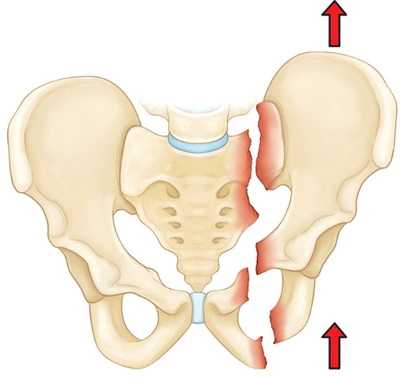

Нестабильные переломы. Данный тип переломов характеризуется нарушением целостности тазового кольца как минимум в двух точках, при котором анатомия таза, как правило, нарушается (происходит смещение фрагментов). Чаще всего такие переломы возникают вследствие высокоэнергетической травмы. К нестабильным переломам относят следующие:

Вертикально-нестабильный перелом. При данном переломе одна половина таза смещается вверх.

- Нестабильные (переломы костей таза, сопровождающиеся нарушением целостности тазового кольца). В зависимости от механизма травмы возможно возникновение вертикально нестабильных и вращательно нестабильных переломов. При вертикально нестабильных переломах костей таза целостность тазового кольца, как правило, нарушается в двух местах: в заднем и переднем отделе. Отломки смещаются в вертикальной плоскости. При вращательно (ротационно) нестабильных переломах со смещением смещение отломков происходит в горизонтальной плоскости.

- Двусторонние переломы таза, особенно в сочетании с разрывом двух или трех сочленений, указывают на переезд.